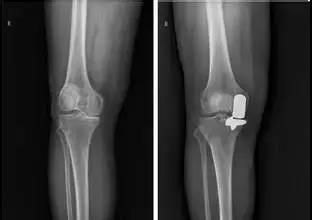

3、 单髁表面置换术:这是保留自己膝关节的一种手术方式,我们称之为保膝手术,但是这种手术具备一定的条件,主要适用于中到重度关节磨损,但磨损尚且局限于胫股关节的前内侧间室、畸形较轻的病人,单髁表面置换术手术相对较小,不改变关节的运动学方式,恢复快,效果好。

4、 全膝关节表面置换术: 全膝关节置换可以 彻底 消除关节疼痛,改善关节功能,是一种成熟且有效的治疗方法, 应用日益广泛。这也是一招解决疼痛的终极治疗方法。 但膝关节置换手术也是对手术技术和经验要求极高的手术,手术效果和手术技术的好坏关系很大,还是要找专业医生做这样的手术。